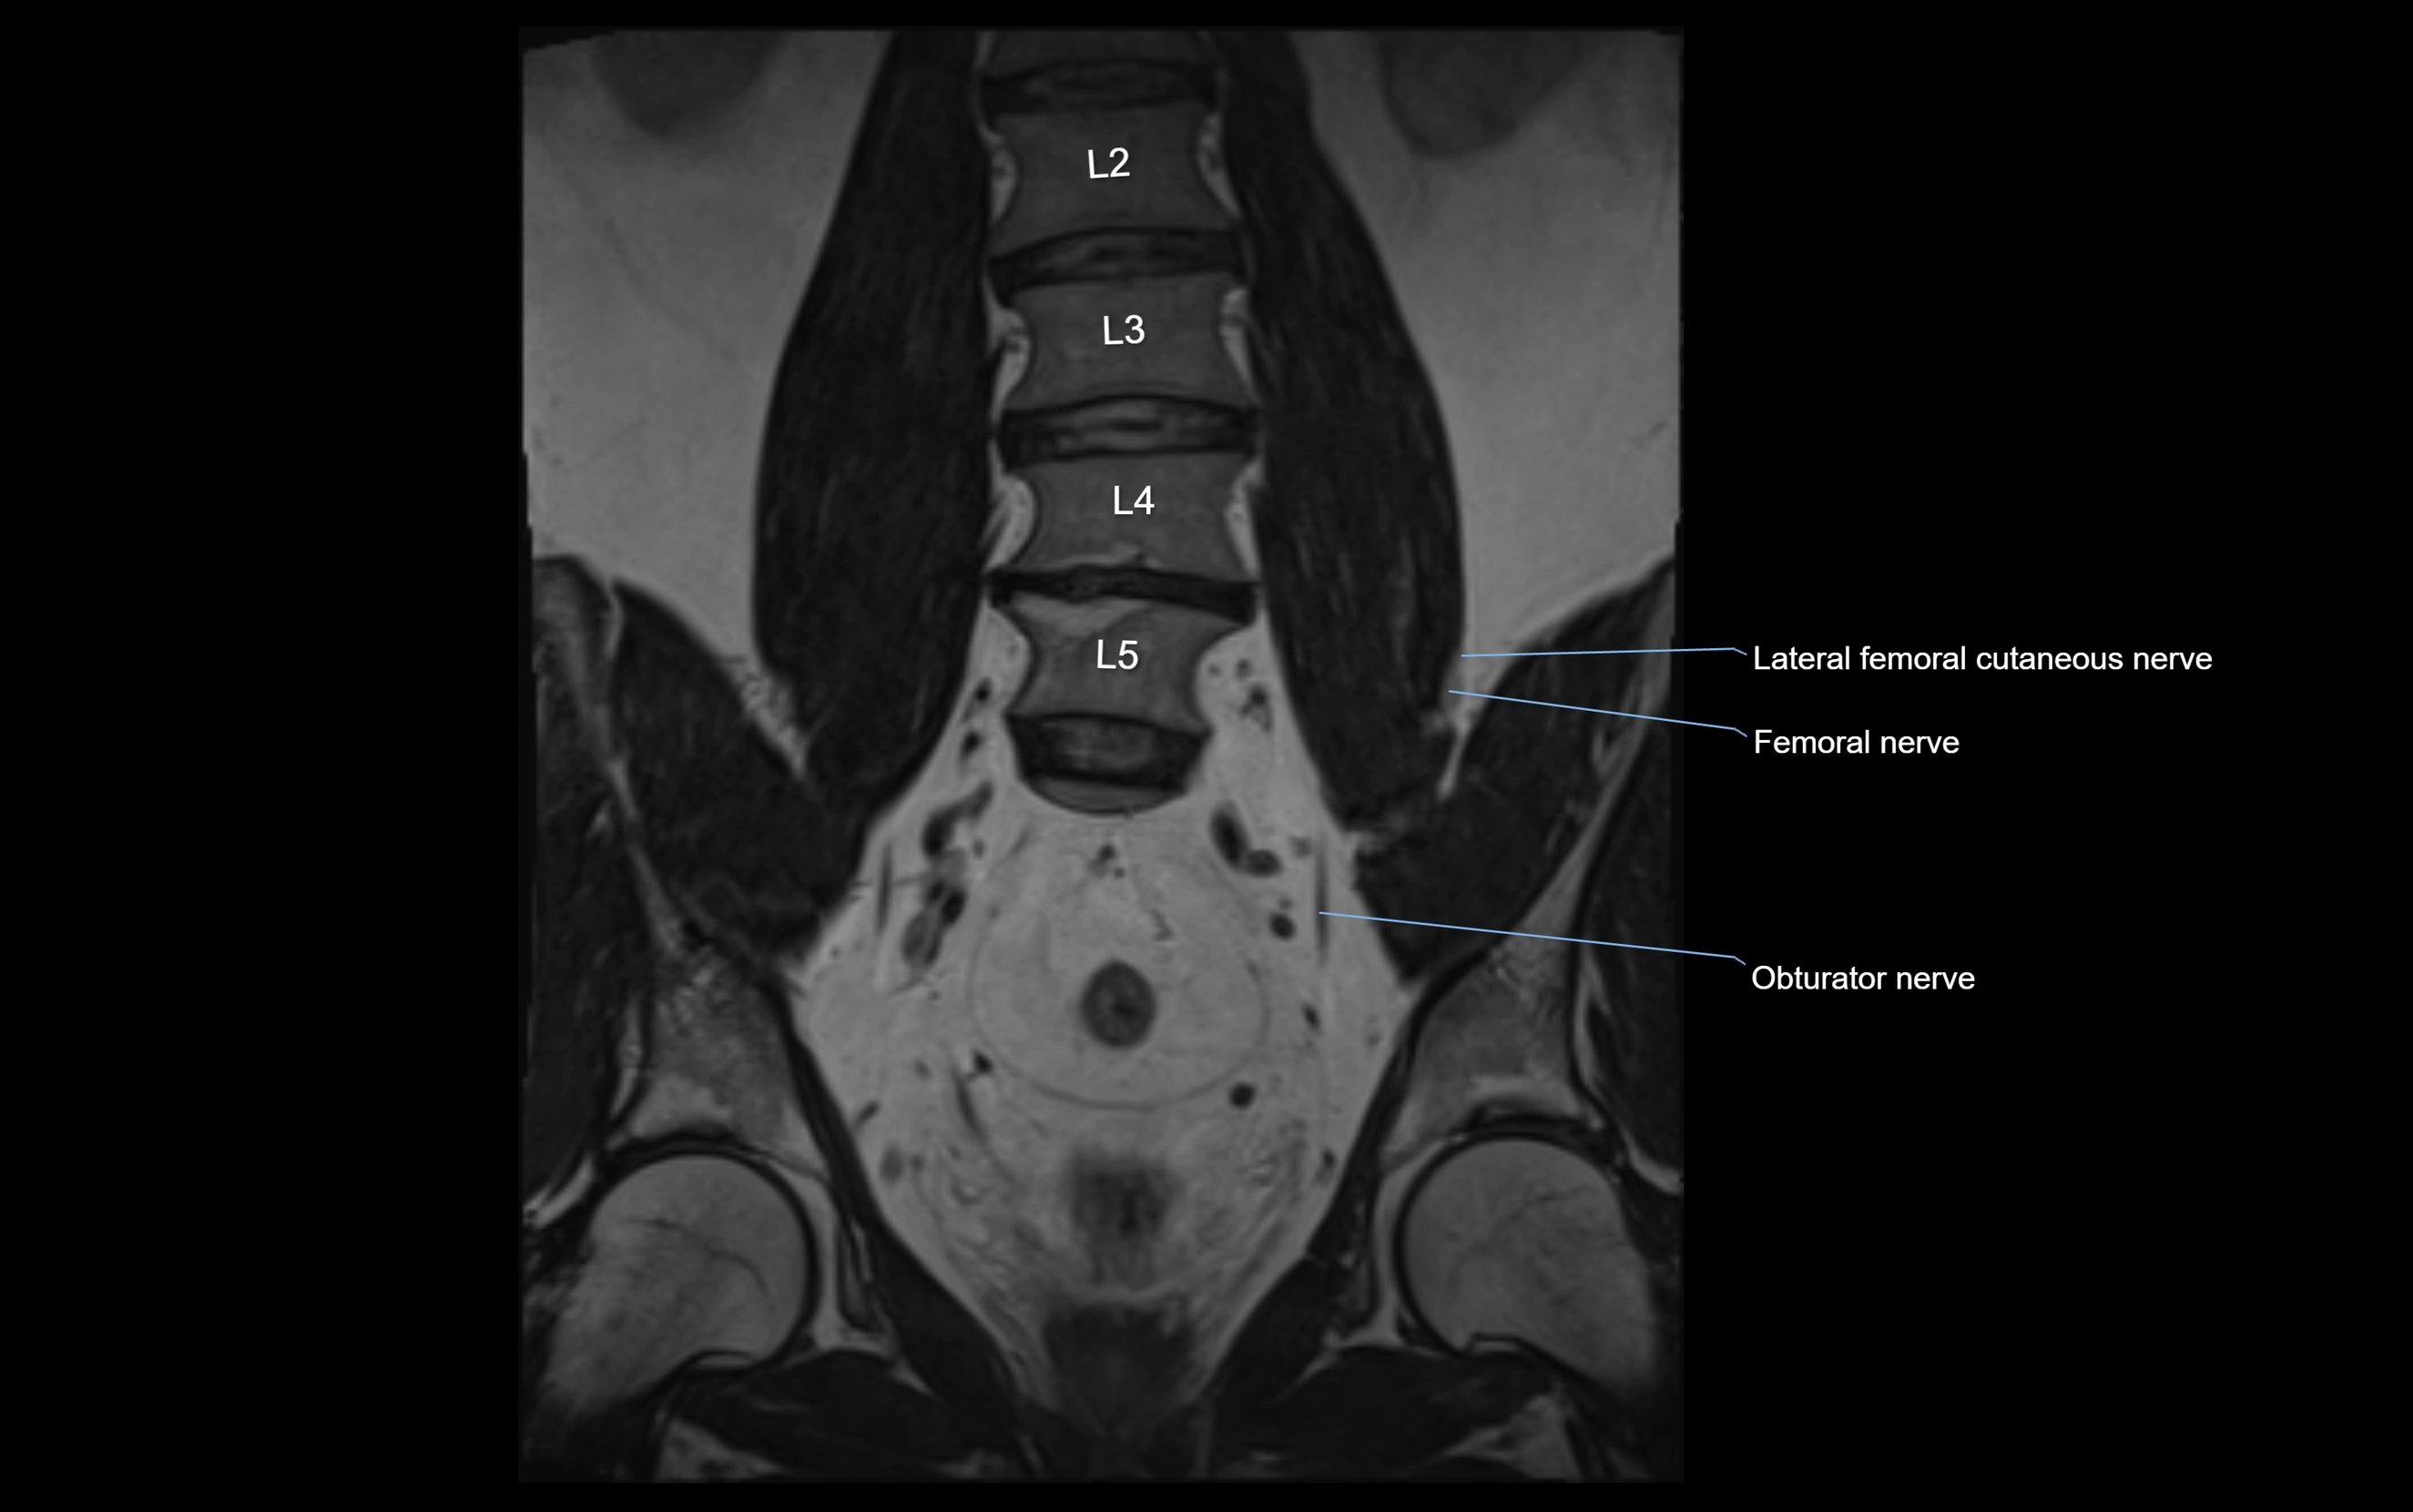

MRI Appearance

T1-weighted images:

• Nerve appears as a very thin low-to-intermediate signal intensity structure

• Surrounded by bright fat, aiding visualization

T2-weighted images:

• Nerve shows intermediate to mildly hyperintense signal compared to muscle

• Pathological involvement appears brighter

STIR (Short Tau Inversion Recovery):

• Normal nerve appears dark

• Inflamed or entrapped nerve appears bright hyperintense

T1 Fat-Sat Post-Contrast:

• Normal nerve enhances minimally

• Pathologic nerve (neuritis, entrapment, tumor infiltration) shows focal or diffuse enhancement

3D T2 SPACE / CISS:

• Nerve appears intermediate to mildly hyperintense compared to muscle

• Surrounded by bright fat or CSF, improving visualization

• Best sequence for mapping small pelvic nerves such as the anococcygeal

MRI image

image